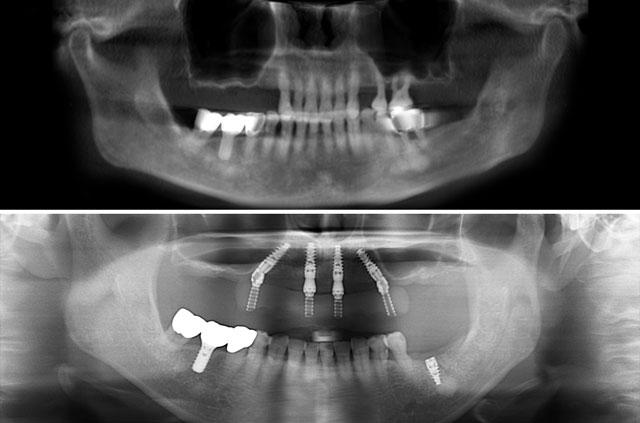

What is the All-on-4 Technique?

All-on-4 is a revolutionary dental implant technique that uses just four strategically placed implants to support a full arch of replacement teeth. The posterior implants are angled at 30-45 degrees to maximize bone contact and avoid anatomical structures like the maxillary sinus or inferior alveolar nerve. This innovative approach allows for immediate loading with a temporary prosthesis, providing same-day teeth and eliminating the need for lengthy healing periods between procedures.